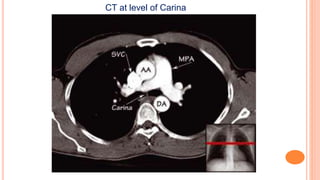

CT at level of Carina

CT at levelof Carina